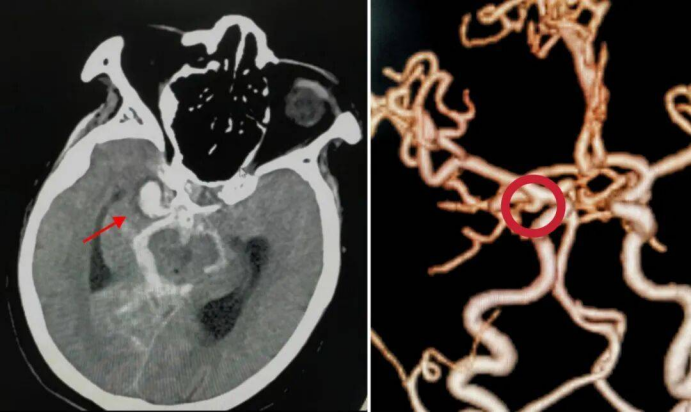

该患者由外院转诊而来,入院时已出现嗜睡、剧烈头痛、呕吐等危急症状,头部CT检查显示其存在广泛蛛网膜下腔出血,病情凶险,随时可能因动脉瘤再次破裂危及生命。面对复杂病情,经开院区神经外科团队迅速响应,联合多学科专家紧急会诊,结合患者病情制定了周密的介入栓塞手术方案。